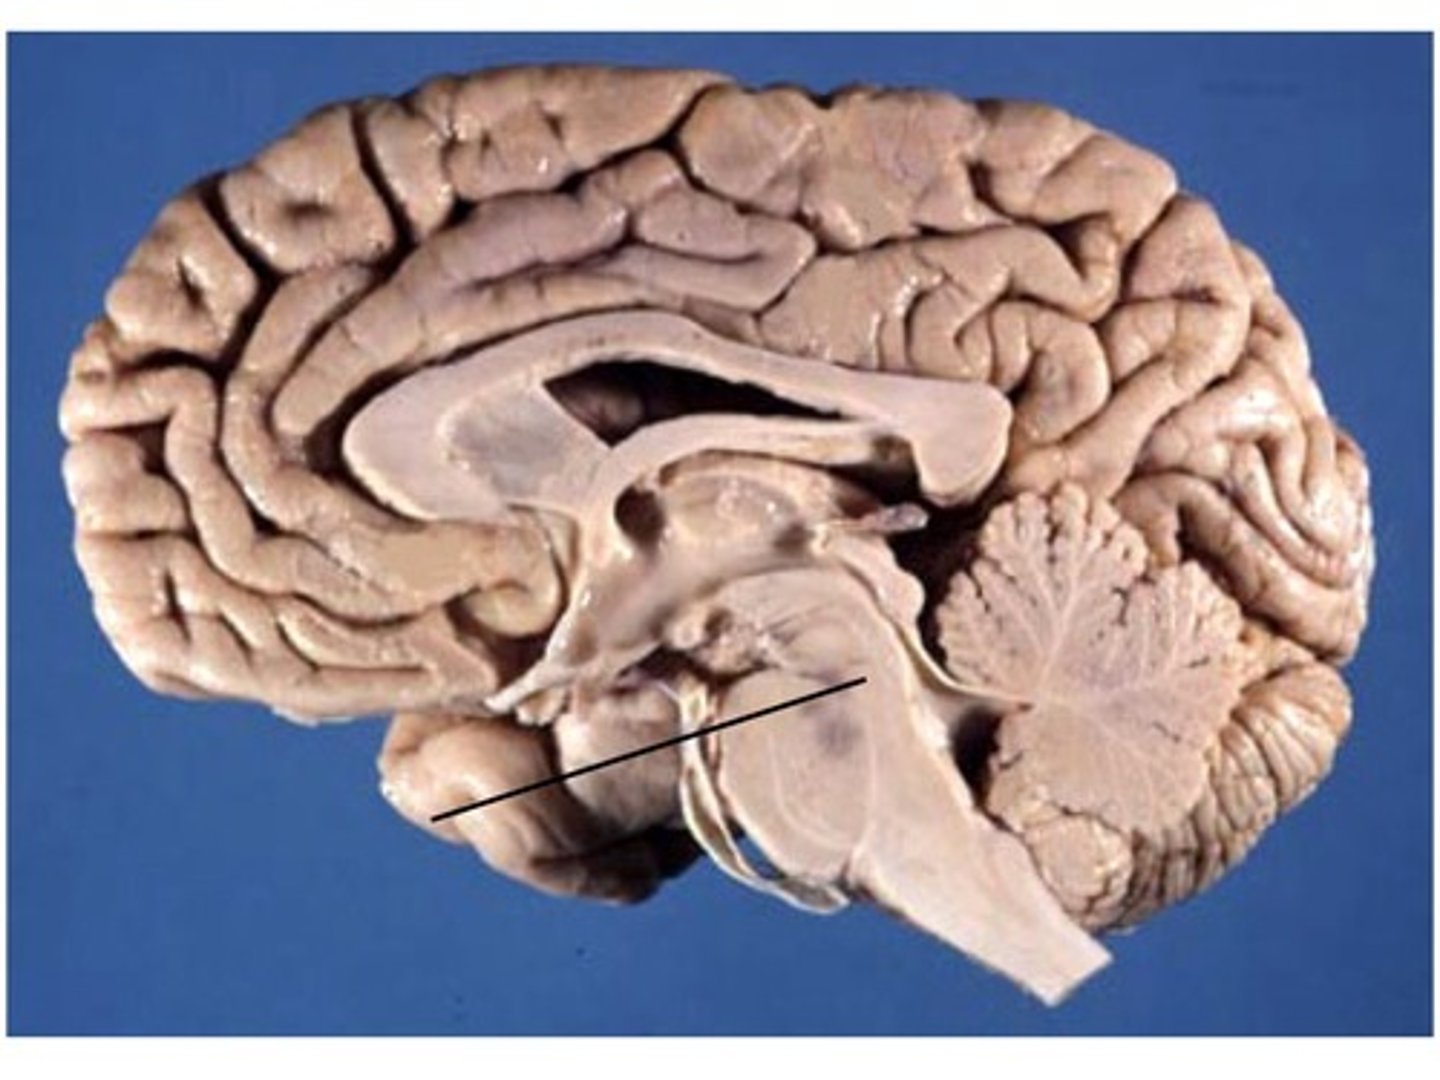

opening running through the midbrain that separates it into the cerebral peduncles and tectum

cerebral aqueduct (iter or aqueduct of Sylvius)

What does the cerebral aqueduct separate the midbrain into?

cerebral peduncles, tectum

part of the midbrain that consists mainly of two (2) pairs of small mounds known collectively as the corpora quadrigemini

tectum

2 pairs of small mounds on the tectum of the midbrain

corpora quadrigemini